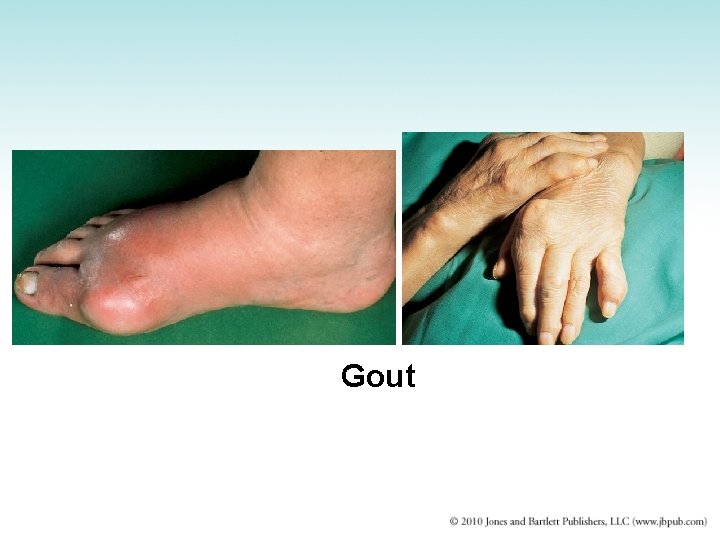

Gout • Disorder of purine metabolism – Uric acid: an insoluble end-product of purine metabolism – Acute episodes caused by precipitation of uric acid crystals in joint fluid – Uric acid stones also may form within kidney and lower urinary tract • Urate nephropathy: urate deposits plug tubules and damage kidneys – Treatment: diet and drugs that lower uric acid

Gout